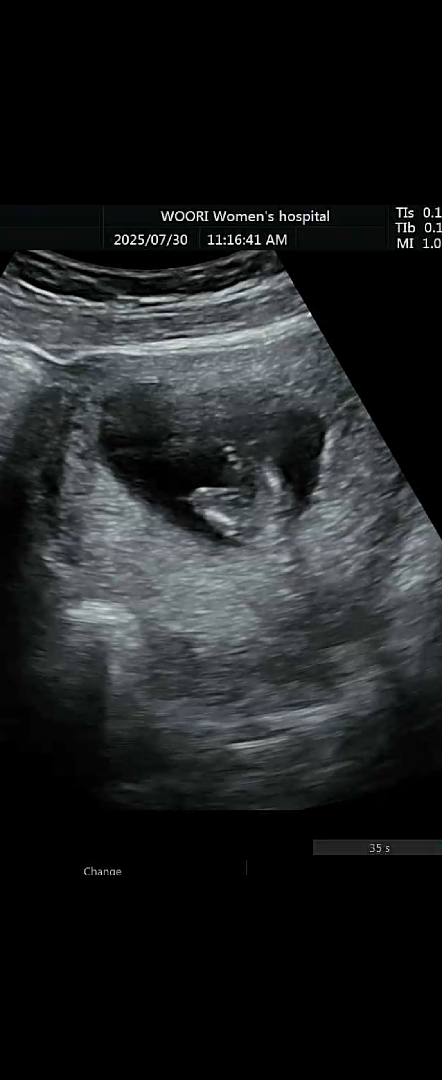

측면샷입니당!!!

12주 4일차 애기 가랑이 사이봐주세용

아무것도 없는거 맞을까용?

딸같아요

없어보이기는 해요